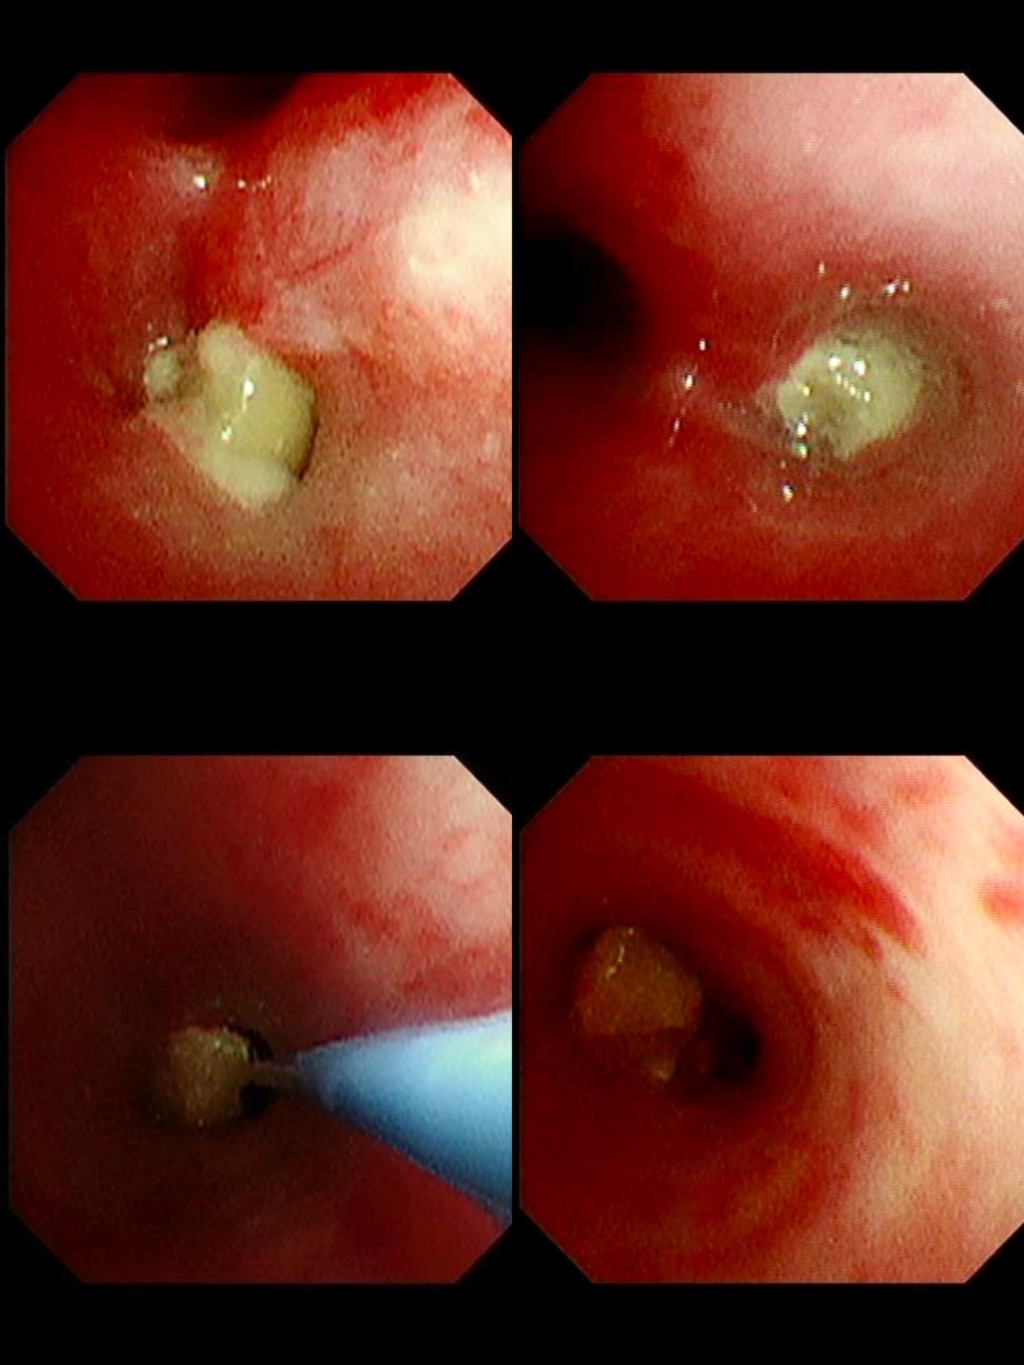

廖穗綾直言,醫師坦言,從來沒有遇過這麼困難的案例,整整將近兩個小時,在狹小氣道裡反覆嘗試,幾乎快要放棄時,那顆「會跳舞的花生」終於彈動了一下,成功網住、夾出,那刻大家都鬆了一口氣。